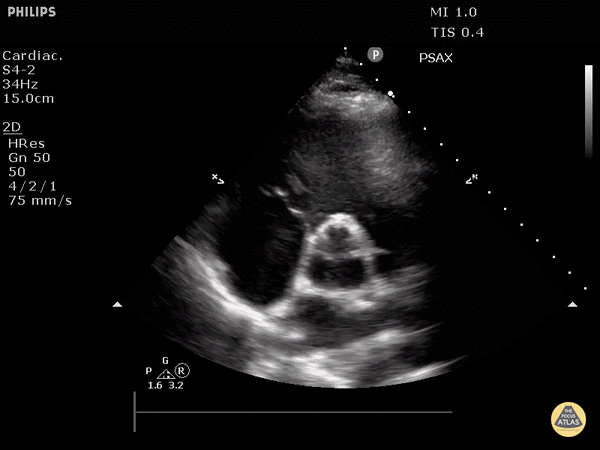

View: Unspecified Parasternal Long Axis Parasternal Short Axis Apical Four-Chamber Subcostal Four-Chamber Subcostal Inferior Vena Cava Right Upper Quadrant Left Upper Quadrant Suprapubic Longitudinal Suprapubic Transverse Subxiphoid Anterior Thoracic Phrenic